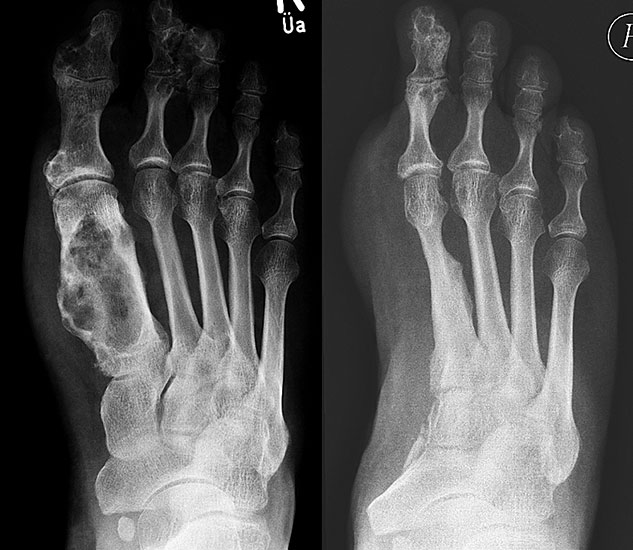

Das solitäre Enchondrom ist von Enchondromatosen, also disseminierten Enchondromen der Extremitäten und des Achsskeletts, abzugrenzen. Die Entartungswahrscheinlichkeit ist für Enchondromatosen wie dem M. Ollier (Abb. 18a und b) oder dem Maffuci-Syndrom deutlich erhöht und wird in der Literatur bis zu 25% angegeben. Klinische und radiologische Hinwiese für eine Entartung beinhalten Kortikalisveränderungen, wie -verdickung, -destruktion und die enossale Kortikalisarrosion, welche in der CT-Bildgebung mehr als 2/3 der Zirkumferenz des betroffenen (Röhren-) Knochens umfasst.

Das primäre, konventionelle Chondrosarkom des Fußes, welches nicht sekundär aus einem Enchondrom oder einer Exostose (exophytäres bzw. exostotisches Chondroarkom) sondern de novo entsteht, zeigt, ähnlich wie das Enchondrom, eine Prädilektion für die kurzen Röhren­knochen (Abb. 19). Das durchschnittliche Alter liegt hier bei 52 Jahren mit einer Bevorzugung des männlichen Geschlechts. In Abhängigkeit der Lokalisation und Graduierung des Tumors umfasst die geeignete operative Therapie die intraläsionale Curettage (G1) bis hin zur Amputation (G3) 34. Das Chondrosarkom ist nicht Strahlen- oder Chemotherapie-sensibel. Eine vollständige chirurgische Resektion bleibt deshalb die einzig sinnvolle Therapiemöglichkeit.